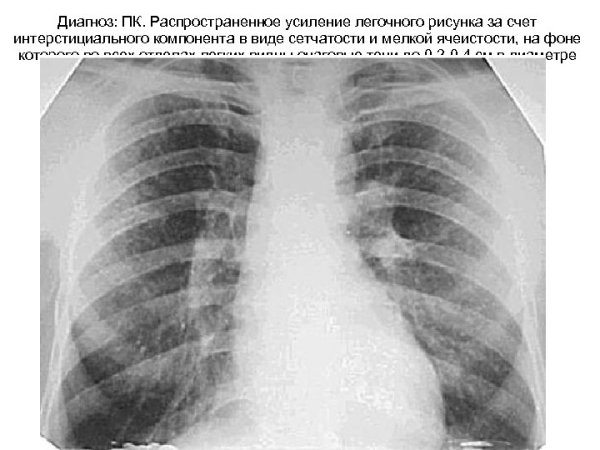

Диффузное усиление легочного рисунка